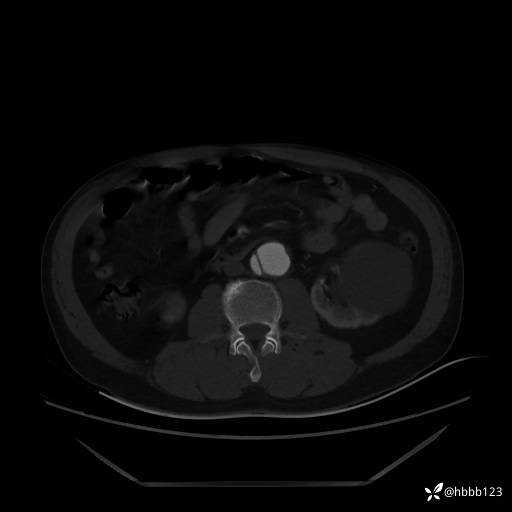

急查胸腹主动脉CTA:

(为方便观察,调至骨窗)

显然是____?